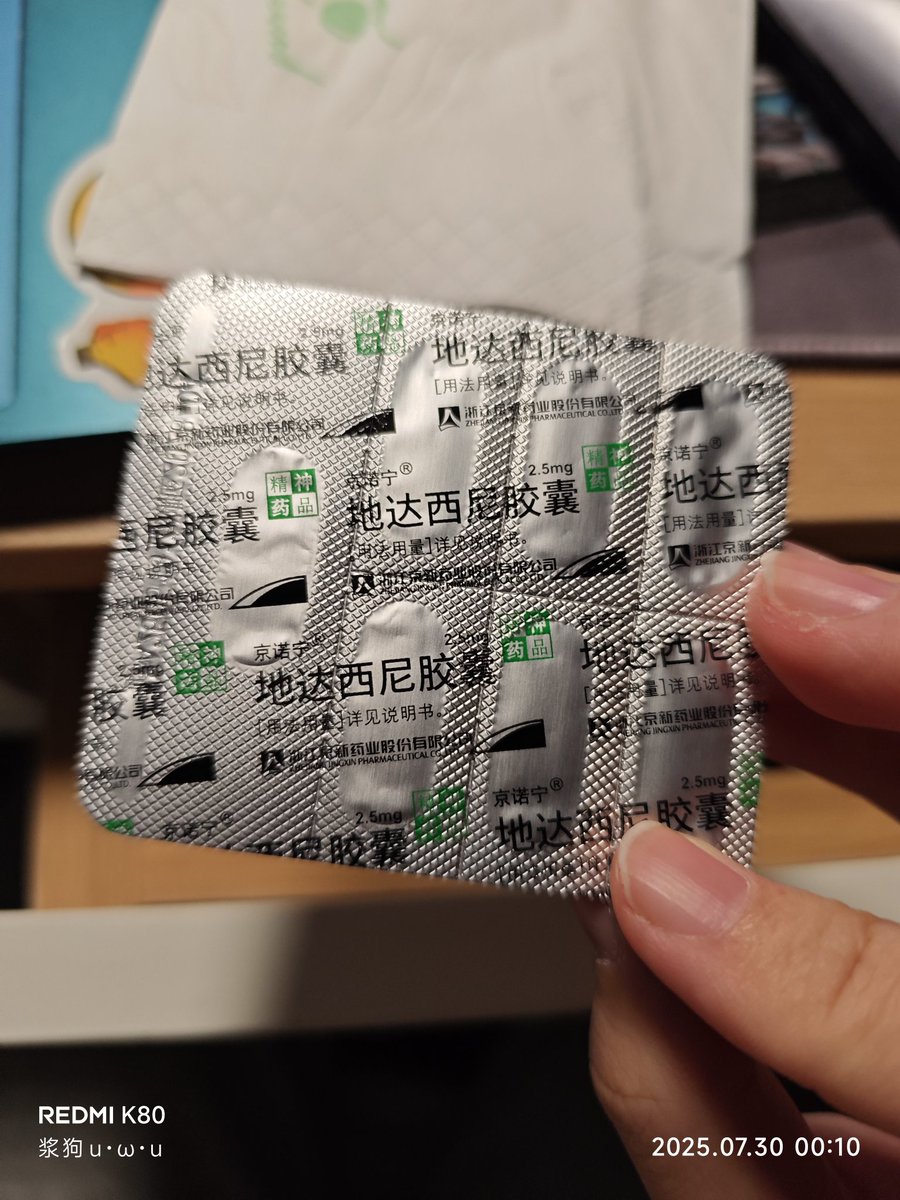

首先,从定义上讲,“反解离(anti-dissociative)”并不是一个标准的医学术语或者广泛认同的药理学分类。在正规资料,比如医学文献、维基百科、精神药理学教科书中,目前并没有“反解离药物”这个正式概念。

看上去像是为了描述某类特定效应而创造的术语(可能是nmda受体活性增强),用来对抗因NMDA受体拮抗剂(比如氯胺酮、DXM、PCP等)引发的解离体验(dissociation)。

那么更常见的是将其归入认知增强剂(cognitive enhancers),特别是改善认知连接性(connectivity)和现实感知(reality testing)的类型。

但其实在药理学上,单纯用“受体激动剂”来逆转“受体拮抗剂”的效应,有时会导致过度激活。

对于NMDA受体而言,过强的NMDA活化本身就与兴奋性毒性(excitotoxicity)和精神病样症状(psychotomimetic effects)有关,比如谷氨酸风暴可以引发严重的焦虑、妄想、乃至癫痫。

也就是说,简单地“激动-解除拮抗”在中枢神经系统是很危险的做法,尤其是对于易感个体(如有精神分裂素质的人)。

科学的处理方式一般是通过更细致的调节,比如微调NMDA/AMPA平衡、调节其他辅助途径(如GABA、5-HT、mGluR受体),而不是简单粗暴地用“NMDA增强剂”去顶回去。

而临床处理药物中毒中,其实医生更常用的做法是保守、支持性的治疗,比如补液,促进代谢,必要时镇静,以及监测生命体征防治并发症。

药物拮抗与受体激动之间,往往牵扯到的是复杂的适应性变化(receptor upregulation/downregulation),

不是简单的“给多一点刺激就能抵消”的关系